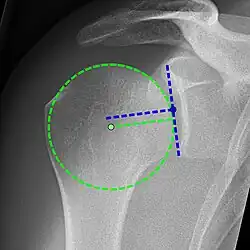

Рентгеновская проекционная рентгенография не может напрямую выявить разрывы вращающей манжеты, «мягких тканей», и, следовательно, обычные рентгеновские лучи не могут исключить повреждение манжеты. Однако косвенные доказательства патологии можно увидеть в случаях, когда одно или несколько сухожилий подверглись дегенеративной кальцификации (кальцифицирующий тендинит). Головка плечевой кости может мигрировать вверх (высоко расположенная головка плечевой кости) вследствие разрыва подостной или комбинированной надостной и подостной мышцами.[44] Миграцию можно измерить расстоянием между:

- Линией, пересекающая центр линии между верхним и нижним краями суставной поверхности суставной впадины (синяя на изображении).

- Центром наиболее подходящего круга, расположенный над суставной поверхностью плечевой кости (зеленый на изображении)

Обычно первый расположен ниже второго, и поэтому переворот указывает на разрыв вращательной манжеты.[44] Длительный контакт между высоко расположенной головкой плечевой кости и акромионом над ней может привести к обнаружению на рентгеновских снимках износа головки плечевой кости и акромиона или вторичного дегенеративного артрита плечевого сустава, называемого артропатия манжеты.[43] Случайные рентгенологические находки костных шпор в соседнем акромиально-ключичном суставе могут показать костную шпору, растущую от внешнего края ключицы вниз к вращающей манжете. На нижней стороне акромиона также можно увидеть шпоры, которые, как когда-то считали, вызывают прямое истирание вращающей манжеты из-за контактного трения, концепция, которая в настоящее время считается спорной.